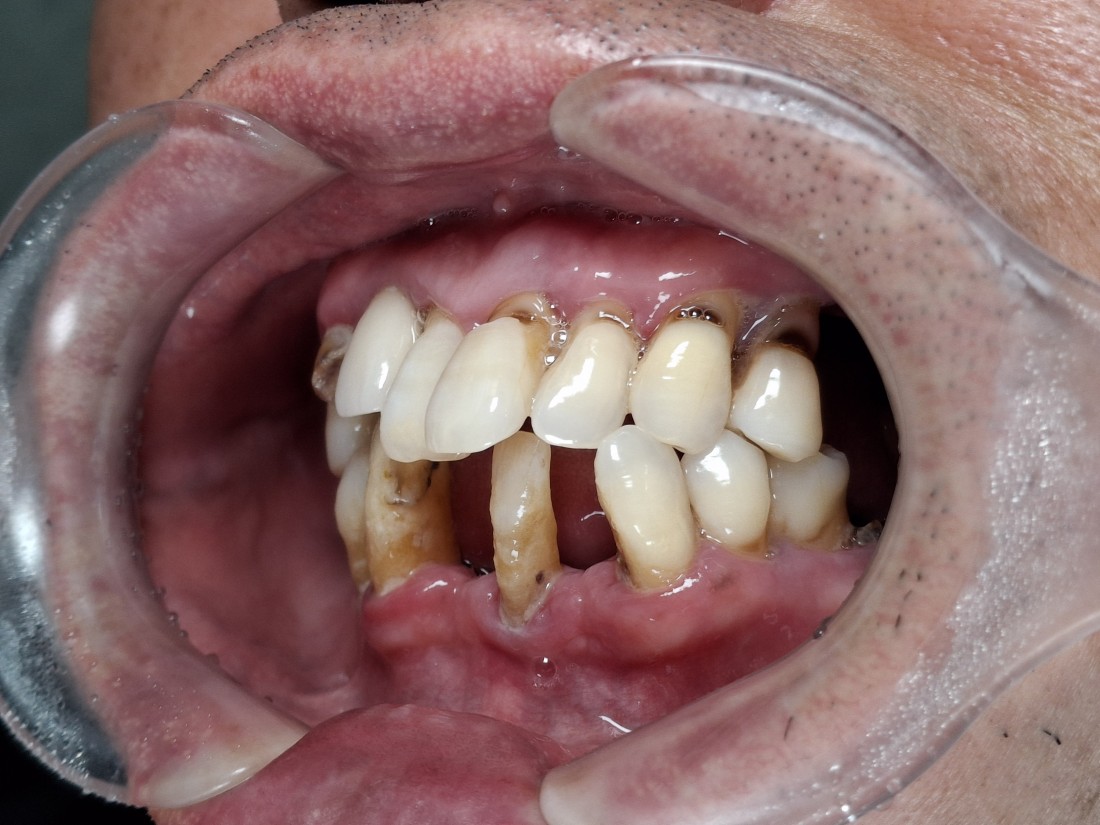

무엇보다도 전체임플란트 중에서

특히 앞니임플란트가

자연스럽고 예쁘게 완성이 되는지

많이 걱정하실텐데요.

광주 전체 임플란트 치과는

4층 자체 치아기공소를 운영하여

보철물 퀄리티를 최상으로 유지합니다.

자연치아보다 더 자연스럽게,

더 잘 씹어질 수 있도록

심미적인 요소와 기능적 요소를

모두 고려하여 제작하고 있으며

불편함이 생기시면 바로 수정이 가능하기 때문에

번거로움 없이 광주 전체임플란트를

완성할 수 있습니다.